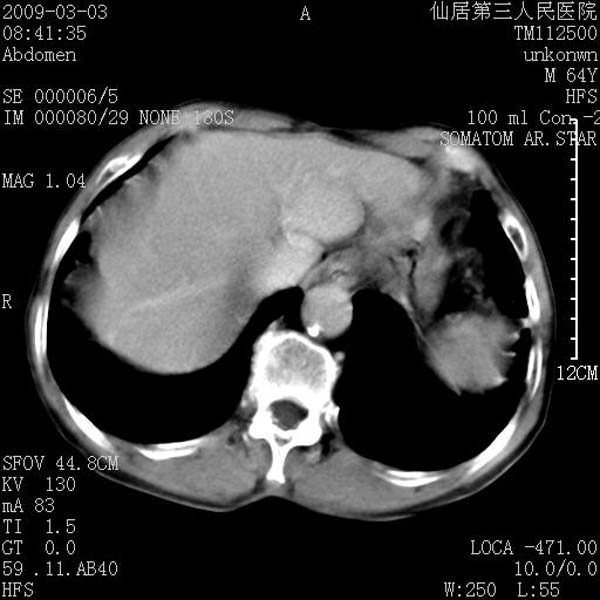

标题: CT18469:男性,64y,体检B超示肝脏低回声肿块,有胃溃疡手术 [打印本页]

患者,男性,64y,体检b超示肝脏低回声肿块,有胃溃疡手术史。

从平扫及增强的特点来看,支持肝脏腺瘤并出血。

支持肝脏腺瘤并出血。期待结果。

ct值呢?感觉没强化,象囊性。

考虑肝静脉韧带裂区良性占位性病变(囊肿?)。

考虑肝囊肿并出血可能性大.

支持肝脏腺瘤并出血。期待结果

考虑高密度囊肿可能性大